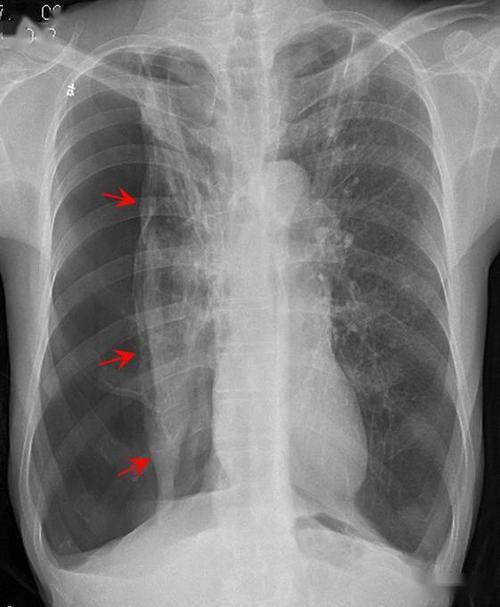

气胸的片子图片,气胸胸片典型图片

典型的结核病人液气胸胸片

气胸胸片典型图片

气胸x线胸片图解

气胸胸片

气胸x线胸片

气胸的x线表现